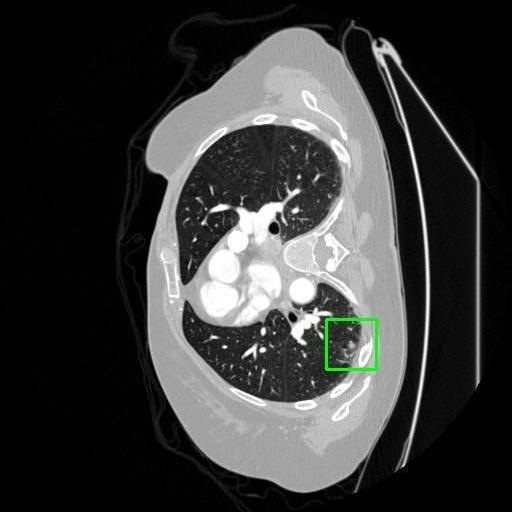

We developed an AI-based system using deep learning models for analyzing lung CT scans to detect and classify pulmonary nodules. We chose the YOLOv11 architecture for its enhanced object detection capability and adapted it specifically for medical imaging, incorporating pixel-level precision and severity classification.

Classification into three severity levels with colored bounding boxes.

Designed a severity classification system that categorizes nodules into null, moderate, and severe using colored bounding boxes, assisting in rapid clinical decision-making.